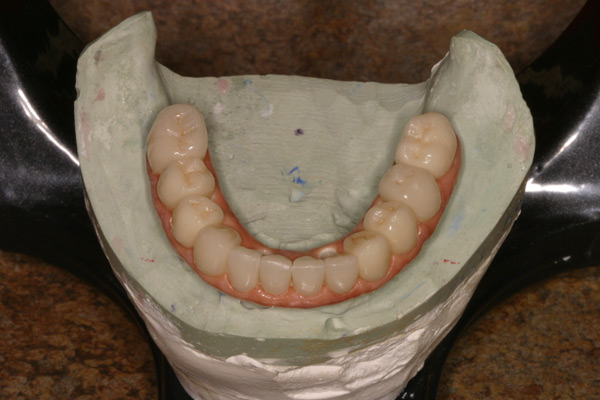

Problem: This patient presented with severe decay and a difficult occlusion/bite. He had teeth that had already been removed.

Plan: Our plan… remove the rest of the teeth and place an upper denture. Place four implants on the lower using guided surgery. Restore with a fixed/hybrid bridge.

A solution to every problem.